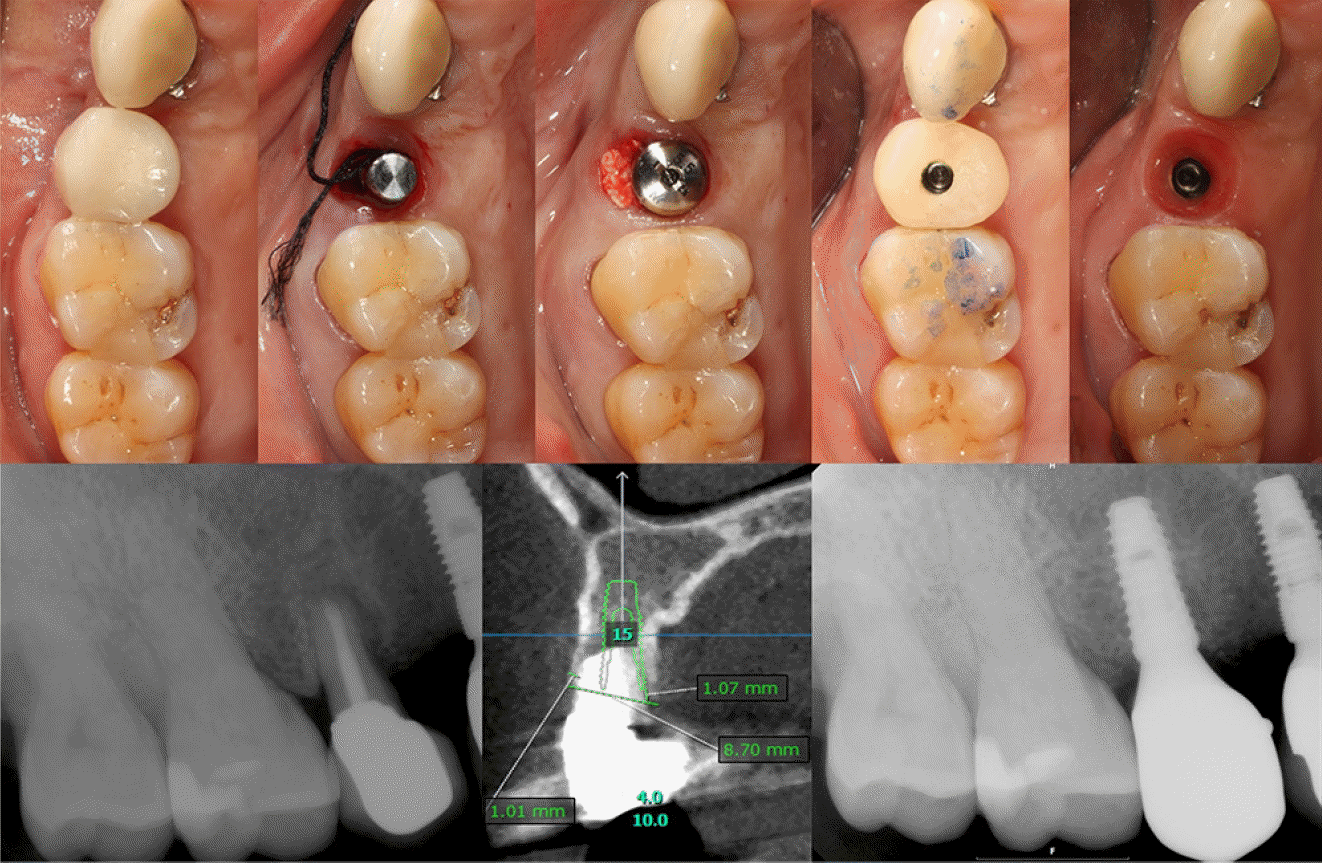

Case 3: Immediate implantation of #16i

A 73-year-old female patient was referred from the Department of Prosthodontics for extraction of the right maxillary first molar and implant placement due to a horizontal fracture of the mesiobuccal root. Preoperative CBCT showed that the buccal and palatal walls were intact, and immediate implantation was planned. After superimposing the impression obtained by an intraoral scanner(Trios 3, 3Shape, Copenhagen, Denmark) to the CBCT scan, a provisional crown was virtually designed using a computer software(Exocad, exocad GmbH, Darmstadt, Germany), matched to the crown shape of the existing tooth. The virtual provisional crown was milled from a polymethyl methacrylate(PMMA) block by a milling machine(IDC Mikro 5X, Amann Girrbach, Koblach, Austria), and then adhered to a non-hex type, pre-manufactured polyether ether ketone(PEEK) abutment(Custom Healing Abutment, Osstem, Busan, South Korea) in order to create the SSA, followed by removing the cusps to avoid any unnecessary occlusal interference with the opposing tooth(Figure 3). A 5.0 x 10mm, SLA surfaced implant(TS III, Osstem) was placed in the septal bone area after the atraumatic extraction with the deproteinized bovine bone mineral(Bio-Oss, Geistlich Parma AG, Wolhusen, Switzerland) grafted to the gap defect, and the pre-fabricated SSA was connected to the fixture to secure the surgical site without any suture(Figure 4).Case 4: Immediate implantation of #15i

Case 4: Immediate implantation of #15i

A 53-year-old female patient was referred from the Department of Conservative Dentistry for the extraction and implant placement due to the endodontic failure of the right maxillary second premolar which appeared to have an apical lesion with external root resorption. Virtual implant planning using a computer software(OnDemand3D, CyberMed Inc.) was performed with the CBCT scan. After an atraumatic extraction, active suppuration was not found therefore, an immediate implant placement was proceeded. Following thorough debridement of apical granulation tissue, an SLA-surfaced implant with the size of 4.0 x 10mm(Superline, Dentium) was placed, and porcinederived xenograft(THE Graft, Purgo Biologics) was applied to the gap defect in the buccal and palatal sides, which was secured by a collagen sponge(CollaTape, Zimmer Biomet) and HA(Healing Abutment, Dentium). Just before connecting the HA, the optical impression was taken by the intraoral scanner(Trios 3, 3Shape) with a PMMA scan body(Geo Scanbody, Geo, Uiwang, South Korea) connected to the fixture, and the scan body was virtually converted into a titanium abutment on a computer software(Implant studio, 3Shape) in order to design an SSA and PMMA crown, which were finally fabricated by the milling machine(IDC Mikro 5X, Amann Girrbach)(Figure 5). The next day of the surgery, the SSA and PMMA crown were delivered to the patient, and occlusal adjustment of 4mm or more was conducted to ensure that the crown did not occlude or interfere with the opposing tooth. The whole procedure was summarized in Figure 6.